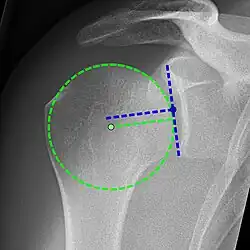

A complete tear of the supraspinatus resulting in a shift upwards of the head of the humerus

Projectional radiograph of normal glenohumeral position.[51]

High-riding humeral head in a rotator cuff tear.

X-ray projectional radiography cannot directly reveal tears of the rotator cuff, a 'soft tissue', and consequently, normal X-rays cannot exclude a damaged cuff. However, indirect evidence of pathology may be seen in instances where one or more of the tendons has undergone degenerative calcification (calcific tendinitis). The humeral head may migrate upward (high-riding humeral head) secondary to tears of the infraspinatus, or combined tears of the supraspinatus and infraspinatus.[51] The migration can be measured by the distance between:

• A line crossing the center of a line between the superior and inferior rims of the glenoid articular surface (blue in image).

• The center of a "best-fit" circle positioned over the humeral articular surface (green in image)

Normally, the former is positioned inferiorly to the latter, and a reversal therefore indicates a rotator cuff tear.[51] Prolonged contact between a high-riding humeral head and the acromion above it may lead to X-ray findings of wear on the humeral head and acromion; secondary degenerative arthritis of the glenohumeral joint (the ball and socket joint of the shoulder), called cuff arthropathy, may follow.[50] Incidental X-ray findings of bone spurs at the adjacent acromioclavicular joint may show a bone spur growing from the outer edge of the clavicle downward toward the rotator cuff. Spurs may also be seen on the underside of the acromion, once thought to cause direct fraying of the rotator cuff from contact friction, a concept currently regarded as controversial.